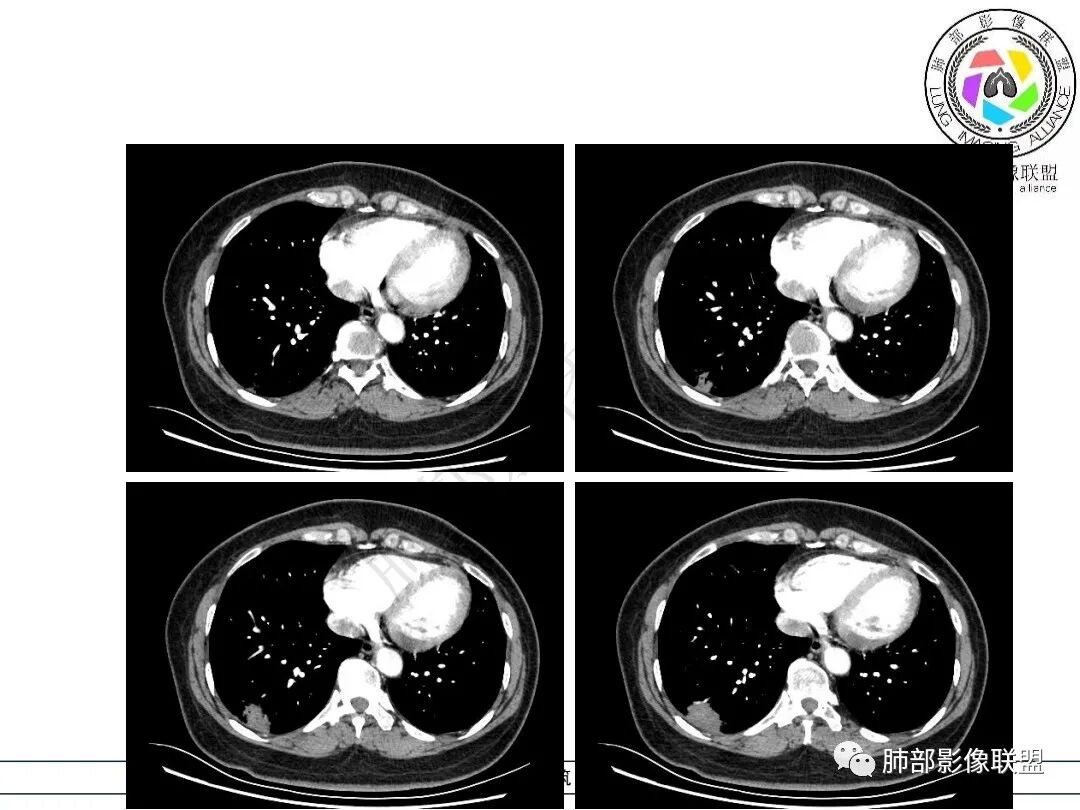

没症状和胸膜痛、有较清晰的GGO、分叶、长轴平行胸膜、重力感、支气管血管未完全侵犯、轻度强化,这些也都是粘液腺癌的特点,可能要考虑到粘液成分的多少、稀稠。

个人认为,相对于隐球菌的亚急性感,粘液腺癌的CT征象其实还是要稍显单一些

是的,病灶远端增厚水肿的脏层胸膜

结节边缘多发淺分叶呈锯齿状也是腺癌的一个特点。